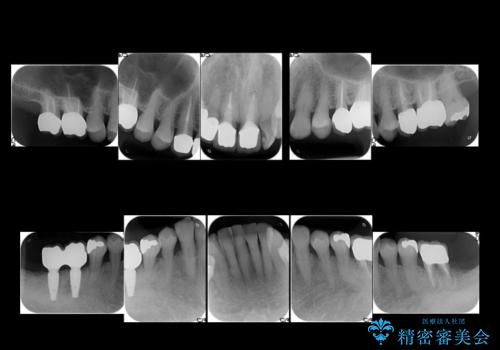

また、上顎前歯以外の根の治療のやり直しを行いました。

上顎前歯は他院で根管治療とセラミックを行なったとのことで、歯肉縁下形成のため、歯肉の腫れが治りにくい状況でしたがやり直しは希望されませんでした。

左下に関しては、経過観察を行い、歯が割れたりした場合にインプラントを考えることになりました。

セラミックが欠けるのを防ぐため、また、左上7は対合歯がなく挺出してしまうのを防ぐため、ナイトガードを就寝時に装着していただいています。

大臼歯の再根管治療は、銀座院院長の林先生にお願いしています。